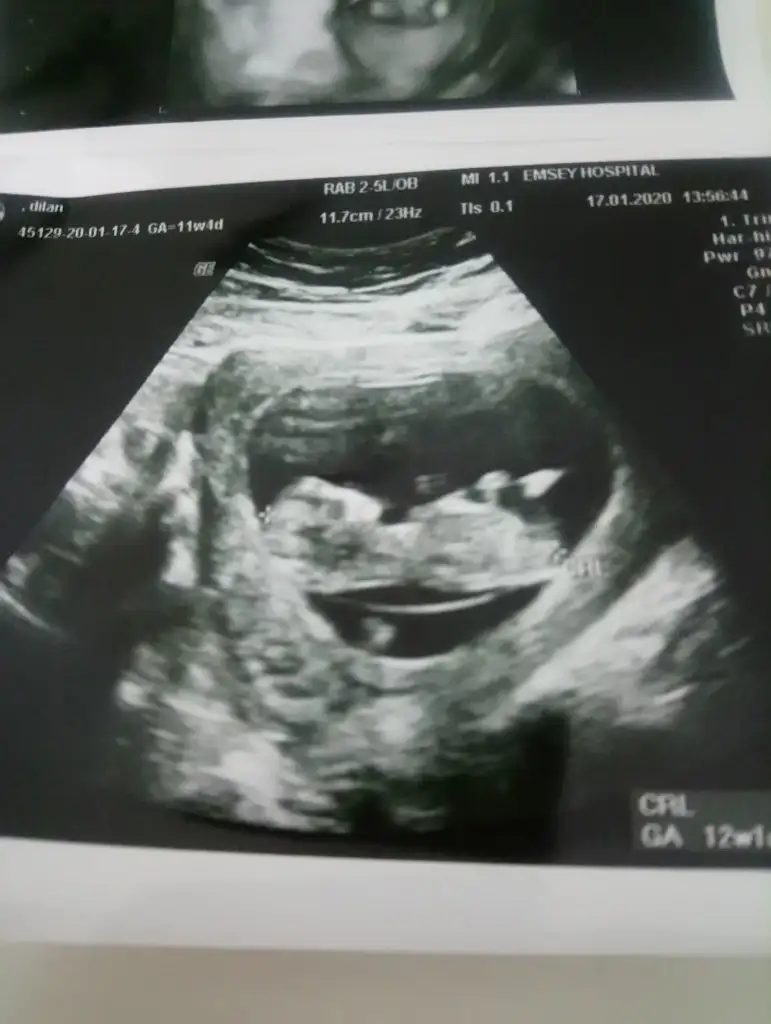

Kız gibi bir usgde en alttaki usgde nubu ne dik ne paralel karşıya bakıyor arada kaldım12+1 bana da tahmin yaparmisiniz ? 3 boyutlu resimde var Eki Görüntüle 2577969 Eki Görüntüle 2577970 Eki Görüntüle 2577971

Erkek diyorum11+5 ikra meyra 11 haftalıkken net değil demiştin bu sefer belli mi acaba bakarmısın sana zahmet![]()

Erkek diyorum